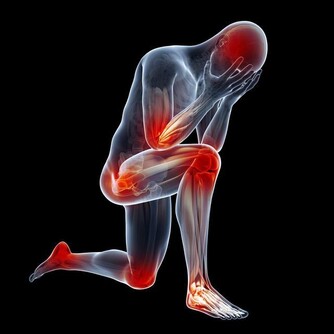

威脅結腸健康的因素依次是:吃肉過多、缺少運動、膳食纖維攝入較少。

保證每天充足的蔬菜和穀物攝入很有必要。

每天進行一定時間的有氧運動,可以防止食物在身體裡逗留過長的時間。

徒步方法很多,晨跑以及下班步行回家都是不錯的方法。